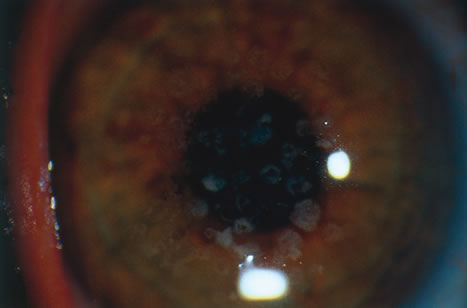

Parasitic Corneal Ulceration

Although corneal infection by Acanthamoeba was described in the 1970s, it was not until the middle 1980s that the disease became a major clinical problem.123 The infection is heralded in soft contact lens wearers with severe pain associated with central corneal ulceration bordered by a ring infiltrate. Characteristically, a clear zone exists between the infiltrate and the limbus. The organisms tend to spread along a plane of relative decreased resistance in the perineural space of corneal sensory nerves rather than penetrate through the denser corneal stroma.124 Inflammation induces the organism to change from the trophozoite form to the cyst form. The cysts, which protect the organism from most antiparasitic agents, are found in adjacent uninflamed tissue.

The cysts can be seen by hematoxylin-eosin stain, PAS, or GMS as a faintly staining spherical body approximately 10 μm in diameter. The cysts may be distributed throughout the corneal tissue but tend to be located away from the site of the most intense inflammation. Superficial scrapings are diagnostic with Calcofluor white, a stain that binds strongly with the capsule of the cyst, in up to 92% of cases. This is the most sensitive indicator of Acanthamoeba infection.125